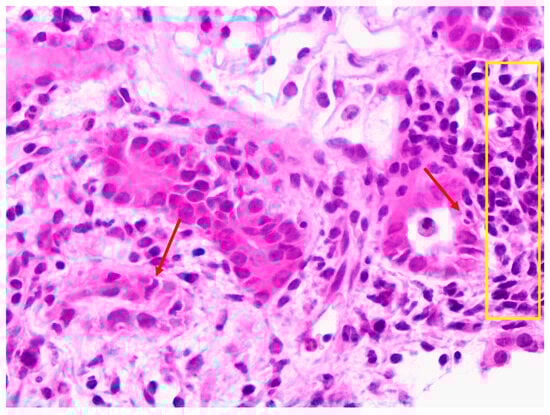

3.1. Case One

3.2. Case Two

3.3. Case Three

3.4. Case Four